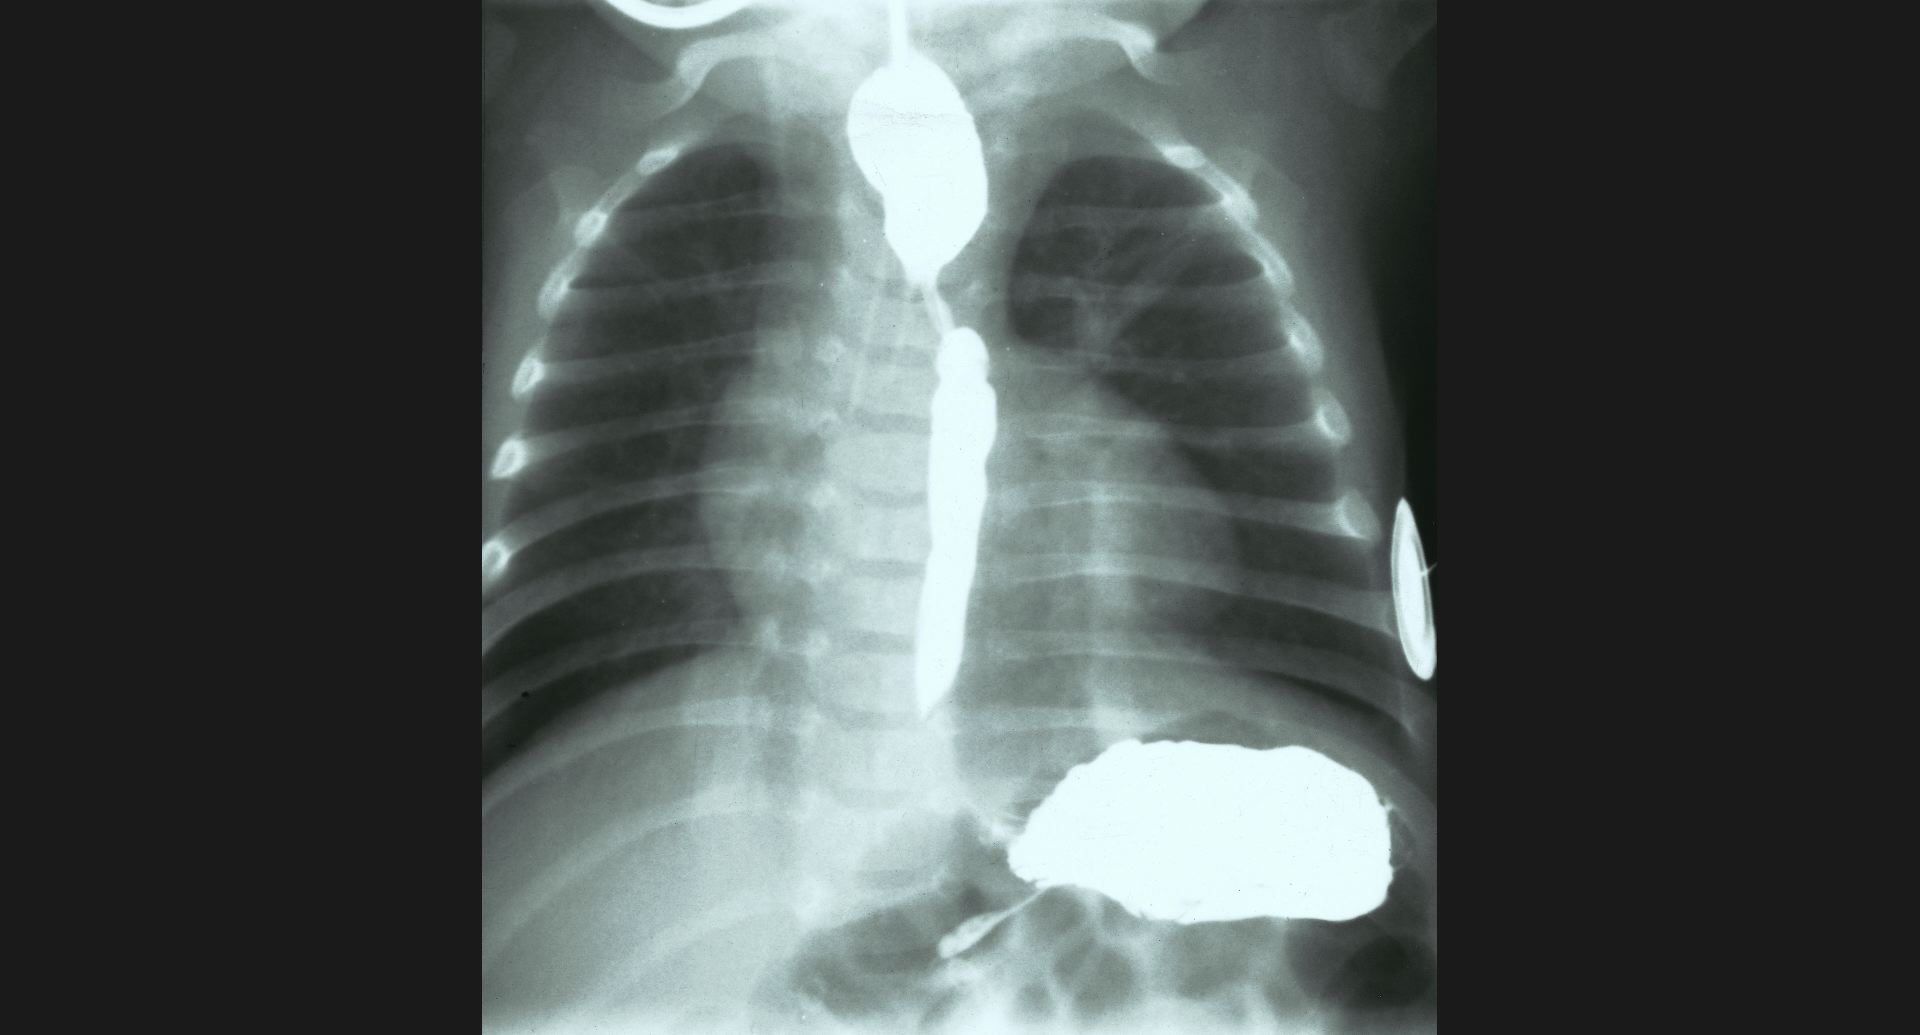

fig.1(117KB) :Alveolar microlithiasis

細かい肺病変、air bronchogram。